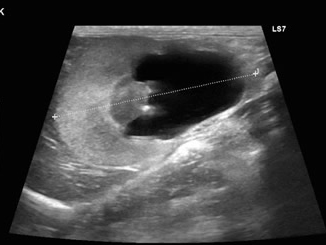

尿管結石が原因で腎臓は水腎症になっていました。

水腎症は改善しました。